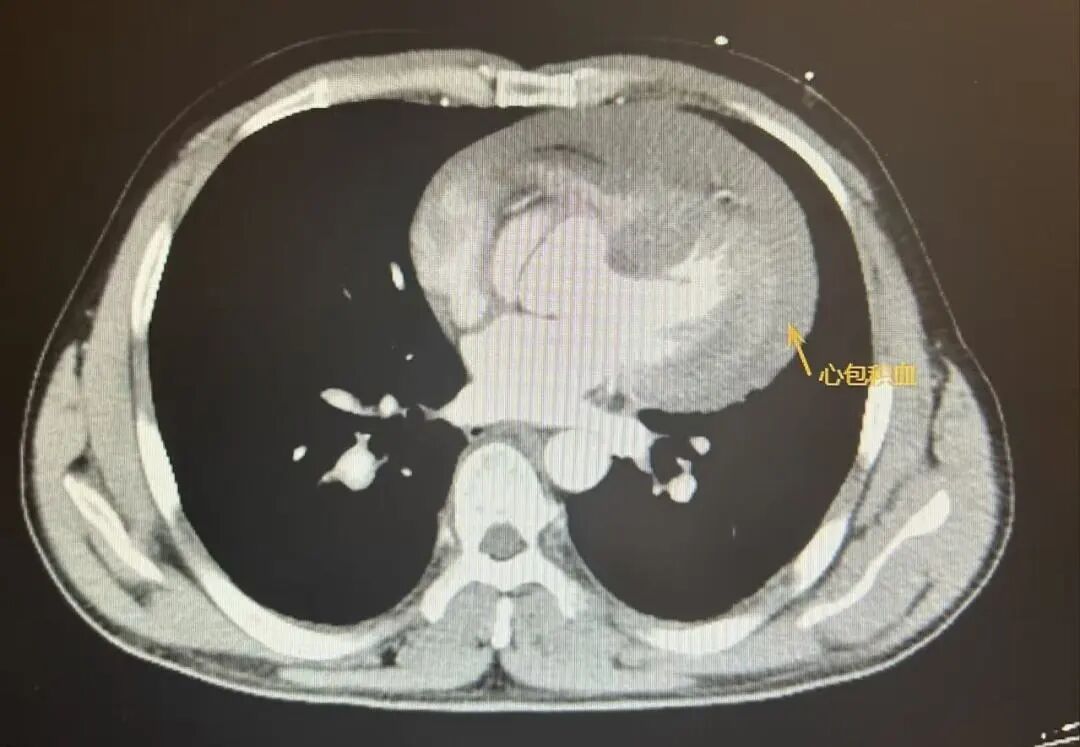

检查结果很快出炉,确诊为 A 型主动脉夹层——简单说就是主动脉内膜撕裂,血液冲进血管壁夹层,如同水管壁「鼓包」,随时可能破裂致命。

更危急的是,患者已出现大量心包积液和心包填塞症状,心脏外层的包膜腔里积满液体,像给心脏套上了「紧箍咒」,压迫心脏无法正常舒张泵血,血压骤降至 50-70 mmHg,生命进入倒计时。